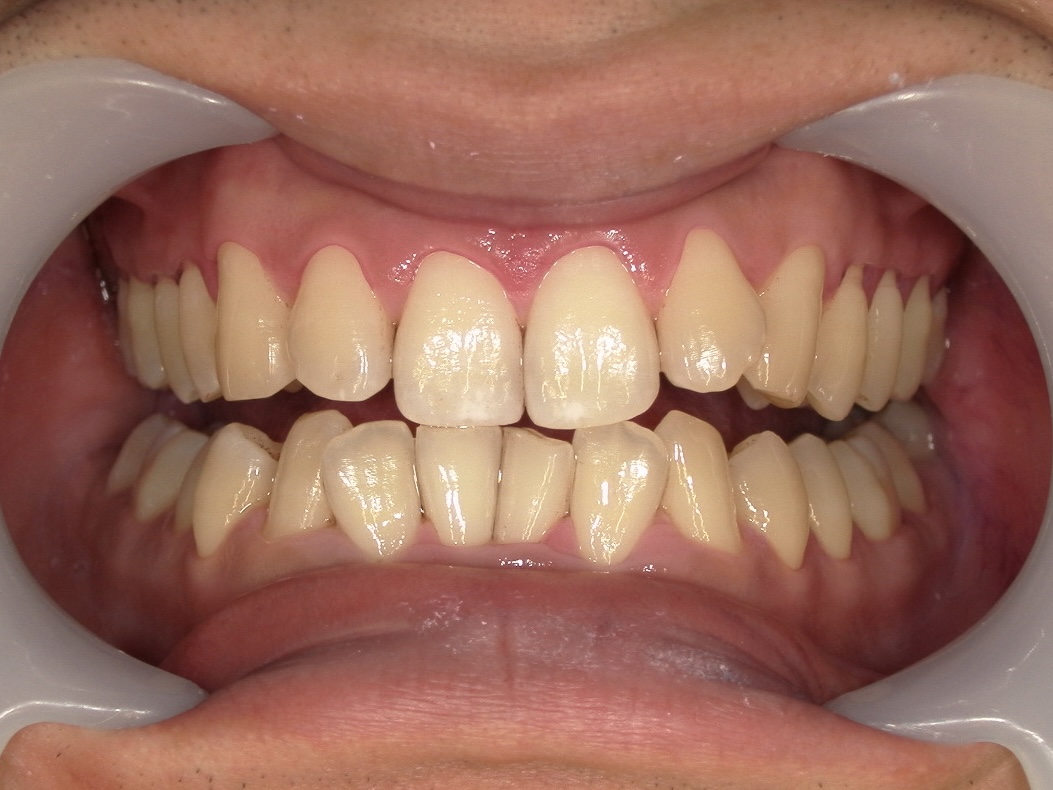

◆クリーニング後の状態

クリーニング後の写真では、歯本来の自然な色調がはっきりと確認でき歯肉の境目もすっきり清潔感が大きく向上しているのが分かります。

特別なホワイトニングを行ったわけではありません。

「汚れをきちんと落としただけ」で、これほど印象が変わります。